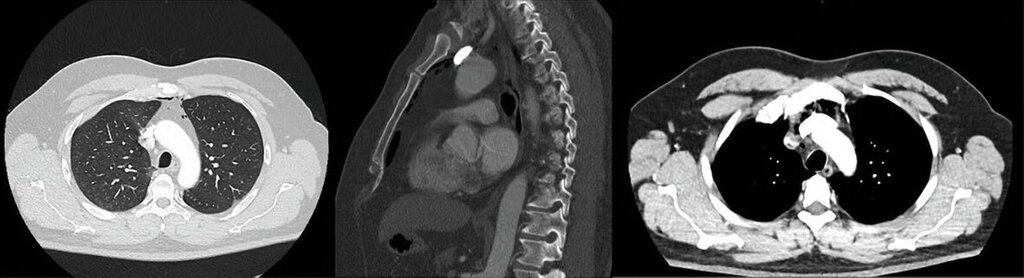

Die klinische Untersuchung ergab eine linksseitige Gesichtsschwellung mit tastbarem subkutanem Krepitus. In der anschließenden Kontrastmittel-gestützten Computertomografie von Kopf, Hals und Thorax zeigte sich ein ausgeprägtes zervikales Weichteilemphysem mit mediastinaler Ausdehnung sowie eine Radix relicta Regio 35 (Abbildungen 1 und 2). Hinweise auf eine Fraktur, einen Abszess oder eine intrathorakale Ursache bestanden nicht. Die radiologischen Befunde legten eine dentogene Ursache nahe, wobei insbesondere die Anwendung von Druckluftinstrumenten im Rahmen der vorangegangenen zahnärztlichen Intervention als auslösender Faktor infrage kam.